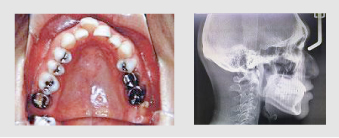

検査

上下の歯型、レントゲン3枚、お口の中のお写真をとります。

それをもとに診断書類を作成し、1ヶ月後に診断を行います。

症例